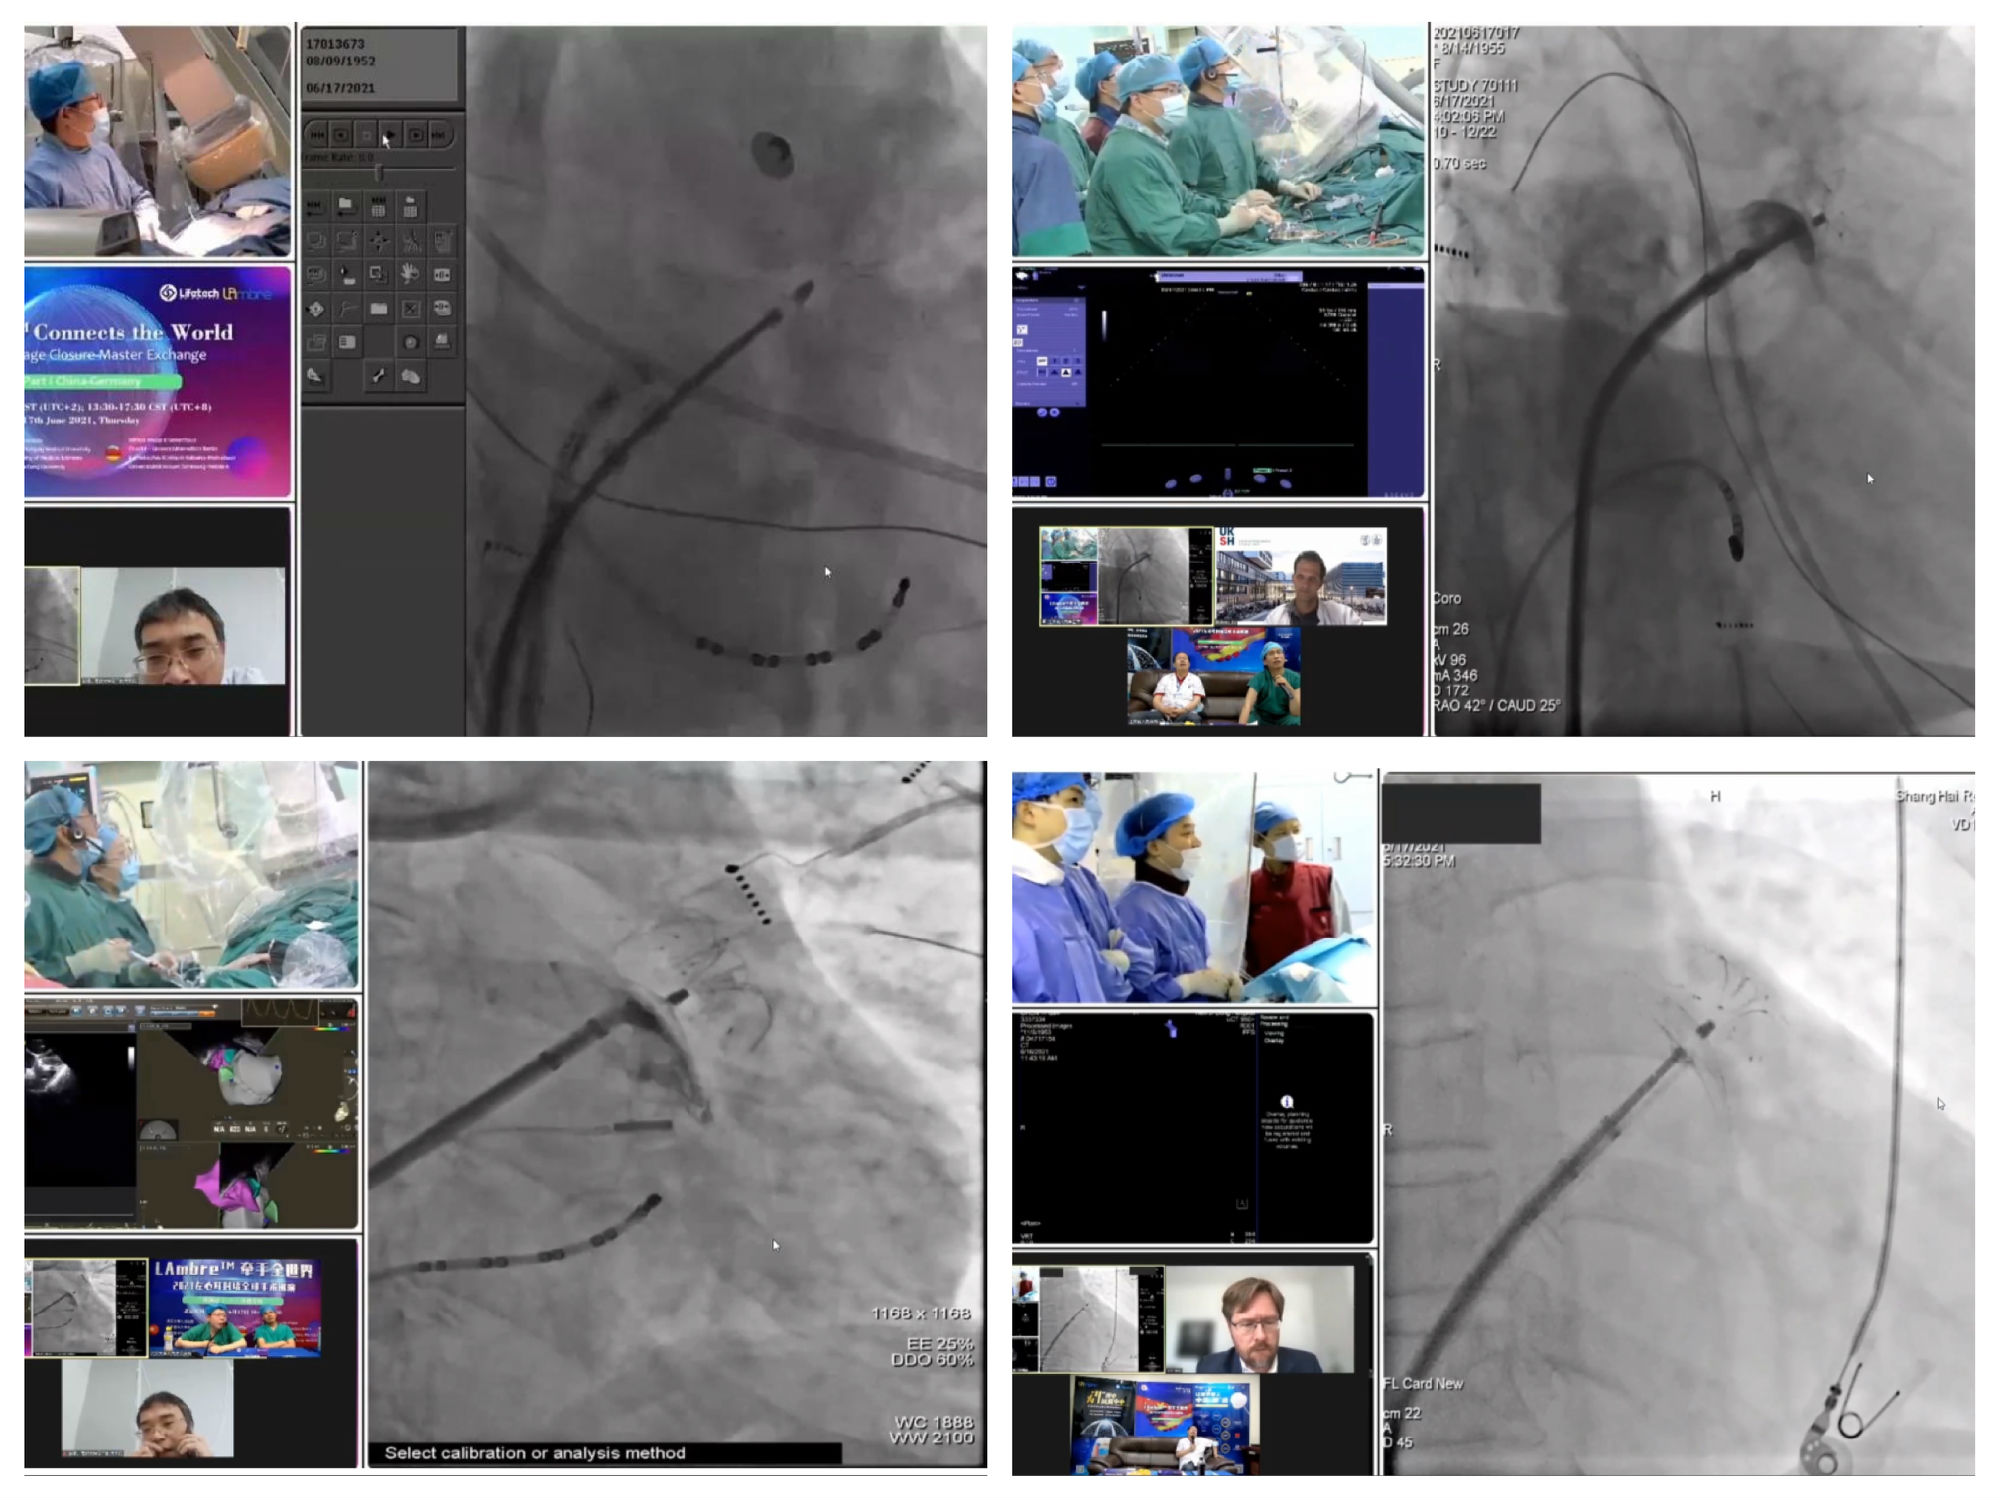

本次手术演示在武汉大学人民医院、南京医科大学附属第一医院、上海交通大学医学院附属仁济医院先后进行,为大家呈现了4台精彩的左心耳封堵手术演示,手术均取得了理想的封堵效果。LAmbre™左心耳封堵器以“独特伞盘设计”、“三重锚定机制”、“型号规格齐全”、“能够适用于各种左心耳解剖结构”等特点,为房颤卒中患者提供了安全有效的手术解决方案。

4台手术均以完美封堵顺利结束